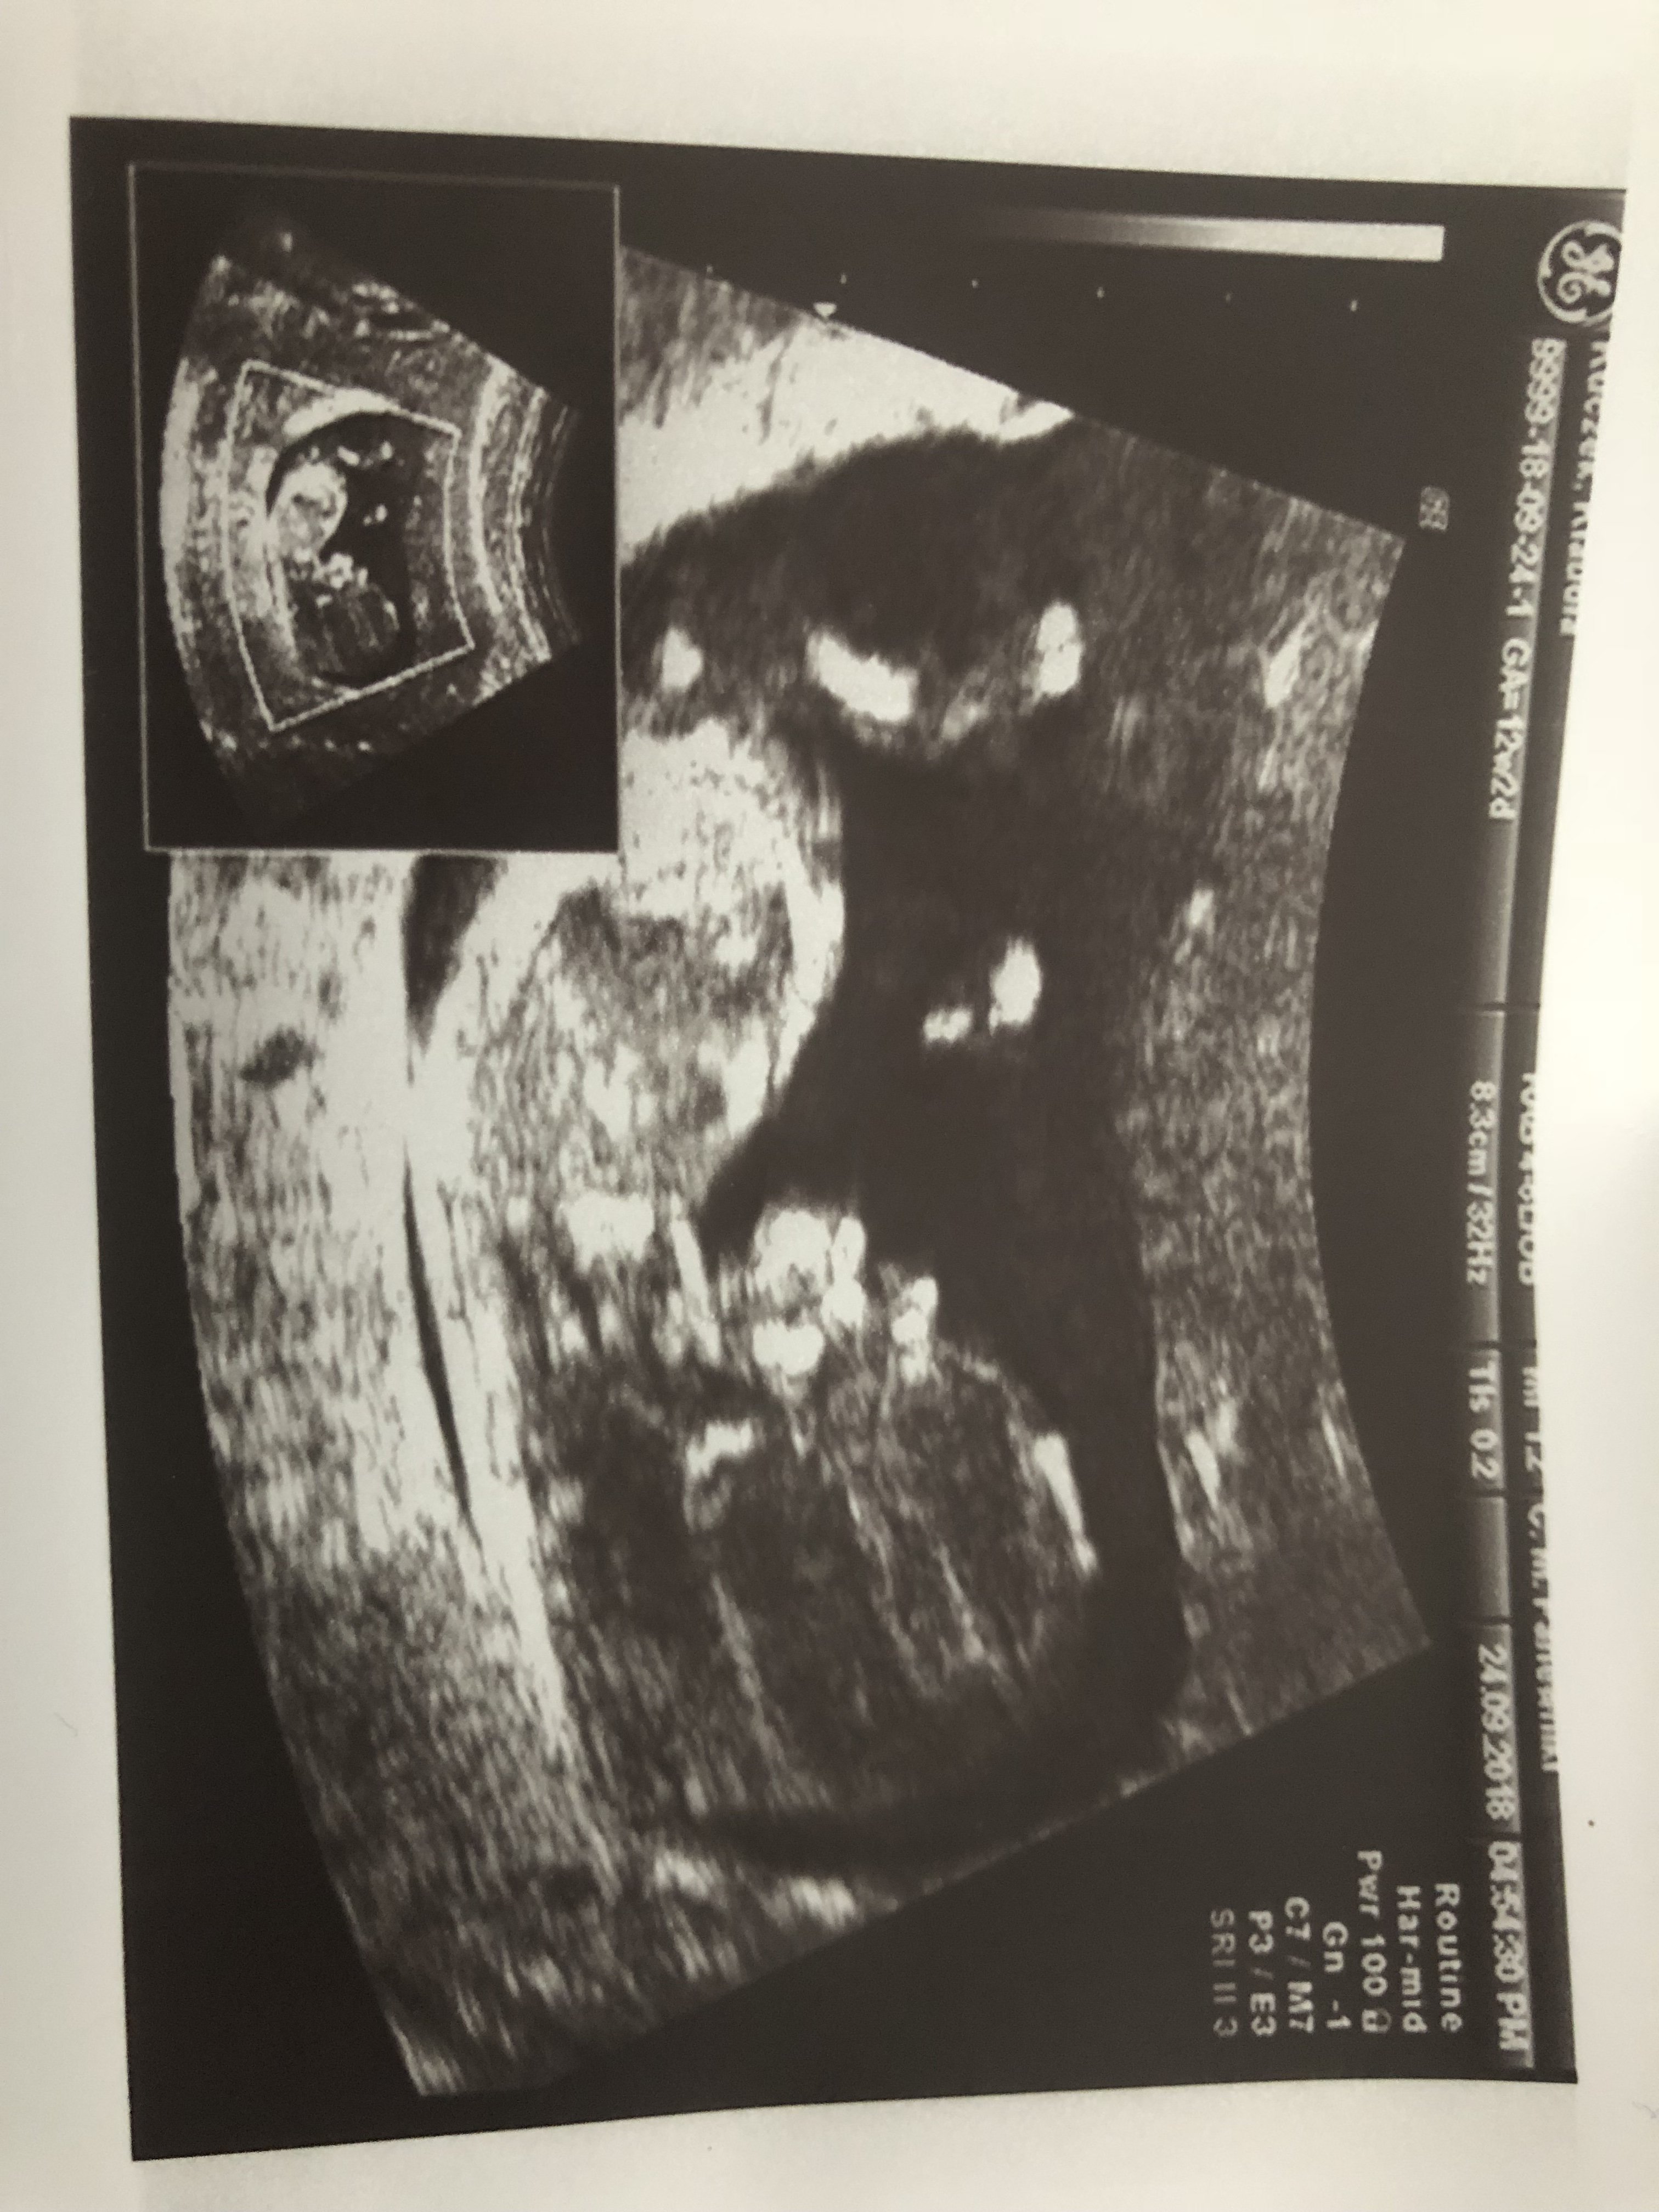

Witam w 19 tygodniu ciąży dowiedziałam się ze będę miała dziewczynkę w 20 tyg okazało się jednak , że to chłopak. Sama już nie wiem bo na jednym usg widać na pewno dziewuche a na drugim chłopca. Może to pempowina ?? Może ktoś mi pomoże rozwiązać ta zagadkę

Witam Was. Może po tych zdjęciach da się odczytać płeć dzidziusia? Dodam że jest to 12+4 tc na prenatalnych Pani dr nie była pewna zajrzała tylko między nóżki na wyrostek nie patrzyła.

Załączniki

• DSC_2504.JPG

DSC_2504.JPG

1,9 MB · Wyświetleń: 408

• DSC_2503.JPG

DSC_2503.JPG

1,9 MB · Wyświetleń: 412

• DSC_2505.JPG

DSC_2505.JPG

1,7 MB · Wyświetleń: 398